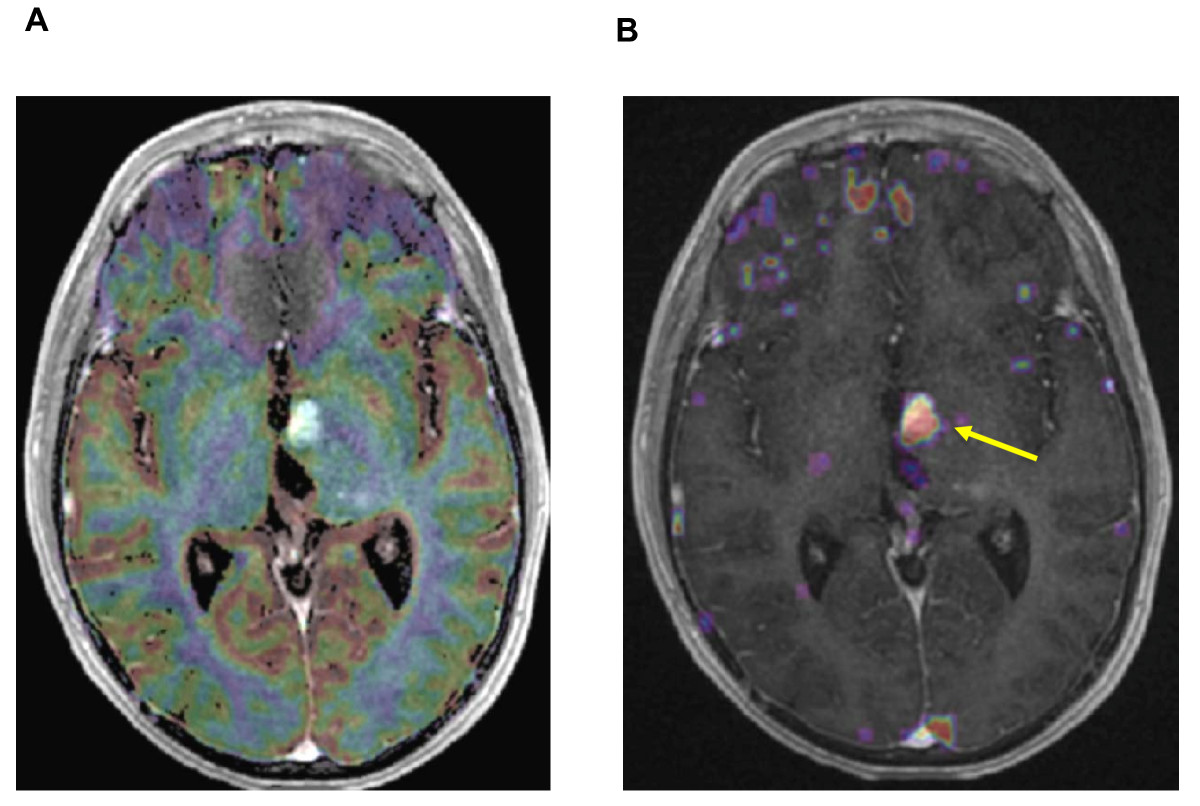

Figure 3. Six months after irradiation: superimposed MR images with T1-weighted sequence after iv Gadolinium injection and co-registered Perfusion (left) and Permability maps (right).

[A] Gradient-echo axial image with color overlay map showing no focus of hyperperfusion in regard of the strong contrast enhancement [B] The superimposed Permeability map with a strong microvascular leakage (yellow arrow) strictly corresponding with the enhanced area in the T1-weighted sequence.